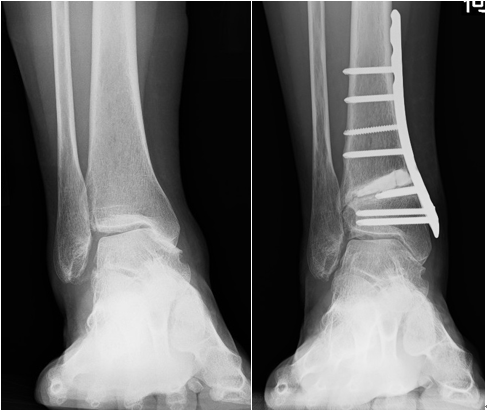

術前 術後

低位脛骨骨切り術は、脛骨を骨切りし関節の形を変えることで、関節の傾きを調整して骨同士の接触の偏りを矯正します。

一般的に関節軟骨が内側に限局された中等度までの関節症に適応になります。当院では、60歳以下の内反型の患者さんを中心に行っています。

入院期間は1~2週間程度で、松葉杖を使用し患肢免荷(手術した足を床につかない)で退院します。術後4~6週程度から短下肢装具を使用し、足を荷重した歩行を開始します。